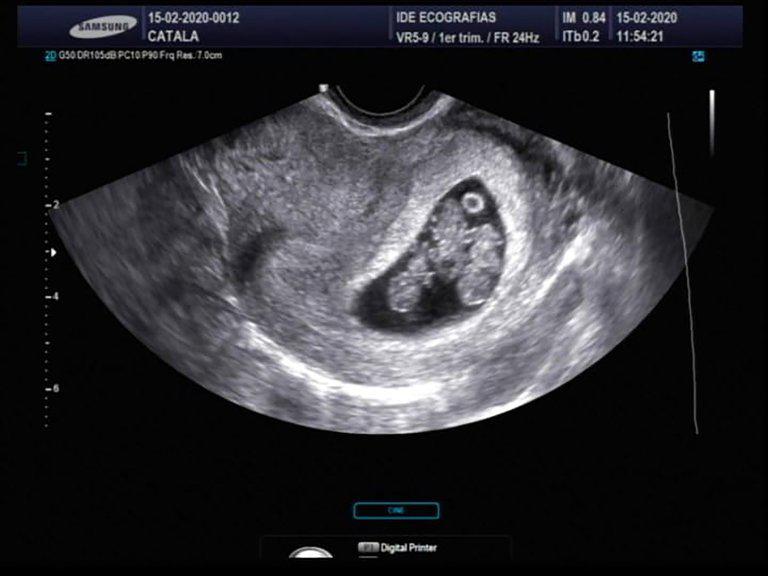

La primera ecografía de Vanina. “Se trata de un embarazo monocorial triamniótico. Los bebés comparten la placenta y todas las características físicas, entre ellas, el sexo y el grupo sanguíneo.

Son genéticamente iguales”, explica María Inés ViscoSegún María Inés Visco, el caso de Vanina es excepcional. “Se trata de un embarazo monocorial triamniótico, lo que significa que las tres niñas son genéticamente idénticas. Por lo general, uno aprende estas cosas en la universidad, pero después es muy difícil encontrarlas en la vida real. Más, cuando se dan de manera natural como en esta pareja”, dice la obstetra.

De acuerdo con Visco este tipo de embarazos múltiples se producen cuando un espermatozoide fecunda un óvulo y queda dividido en tres en la primera etapa de gestación. “Como resultado, los bebés comparten la placenta y todas las características físicas, entre ellas, el sexo y el grupo sanguíneo”, explica la ecografista sin disimular su entusiasmo. Y sigue: “Hay que estar dormido para no enamorarse de esto que está pasando. Toda la comunidad médica del Instituto de Diagnóstico Ecográfico (IDE) está muy emocionada”.